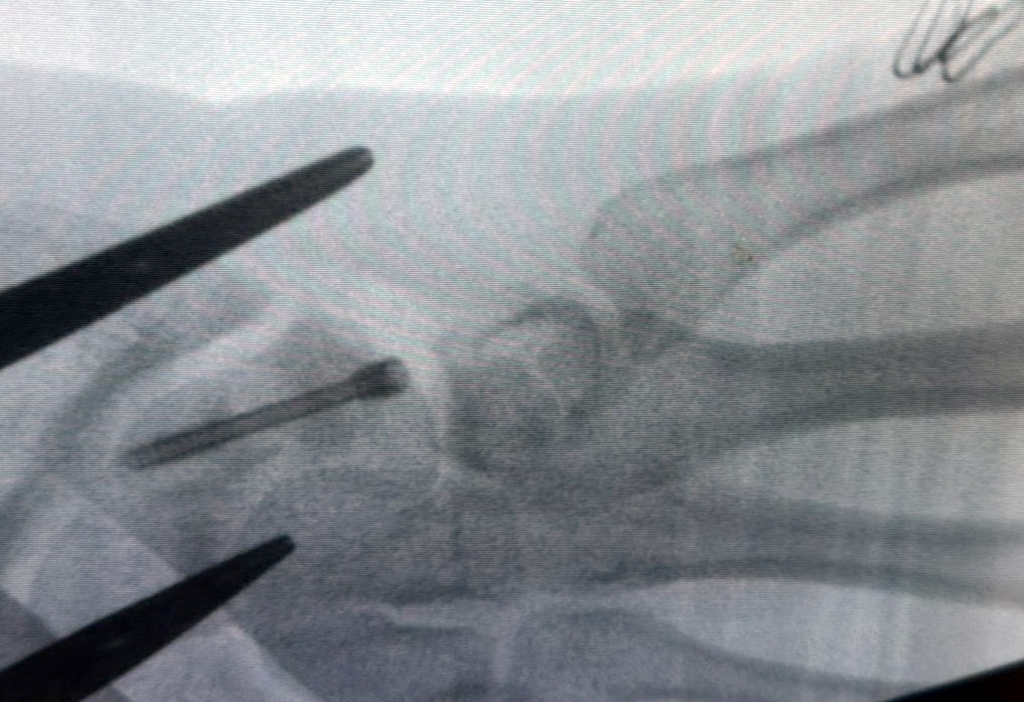

Un adolescent de 16 ani din județul Bihor a ajuns pe masa de operație la Spitalul Clinic Județean de Urgență Bihor, după ce o fractură suferită la fotbal nu s-a vindecat nici la aproape un an de la accident. Este vorba despre o afecțiune rară în ortopedia pediatrică: fractură de os scafoid cu lipsă de consolidare, evoluată spre pseudoartroză.

Investigațiile imagistice, printre care RMN și radiografii, au arătat o fractură de os scafoid drept care nu s-a vindecat, asociată cu o ruptură parțială a ligamentului scafo-lunar. Diagnosticul a fost stabilit de medicul curant, dr. Alexandru Pîrvan.

Intervenția chirurgicală a avut loc în ultimele zile ale anului 2025. Operația a durat aproximativ două ore și jumătate. Medicii au făcut o incizie de circa cinci centimetri, au curățat zona de pseudoartroză și au stabilizat osul cu un șurub Herbert, printr-o tehnică specială. Acest tip de șurub nu are vârf și nu trebuie scos ulterior, el rămânând în corp după vindecarea osului. Evoluția după operație a fost bună.